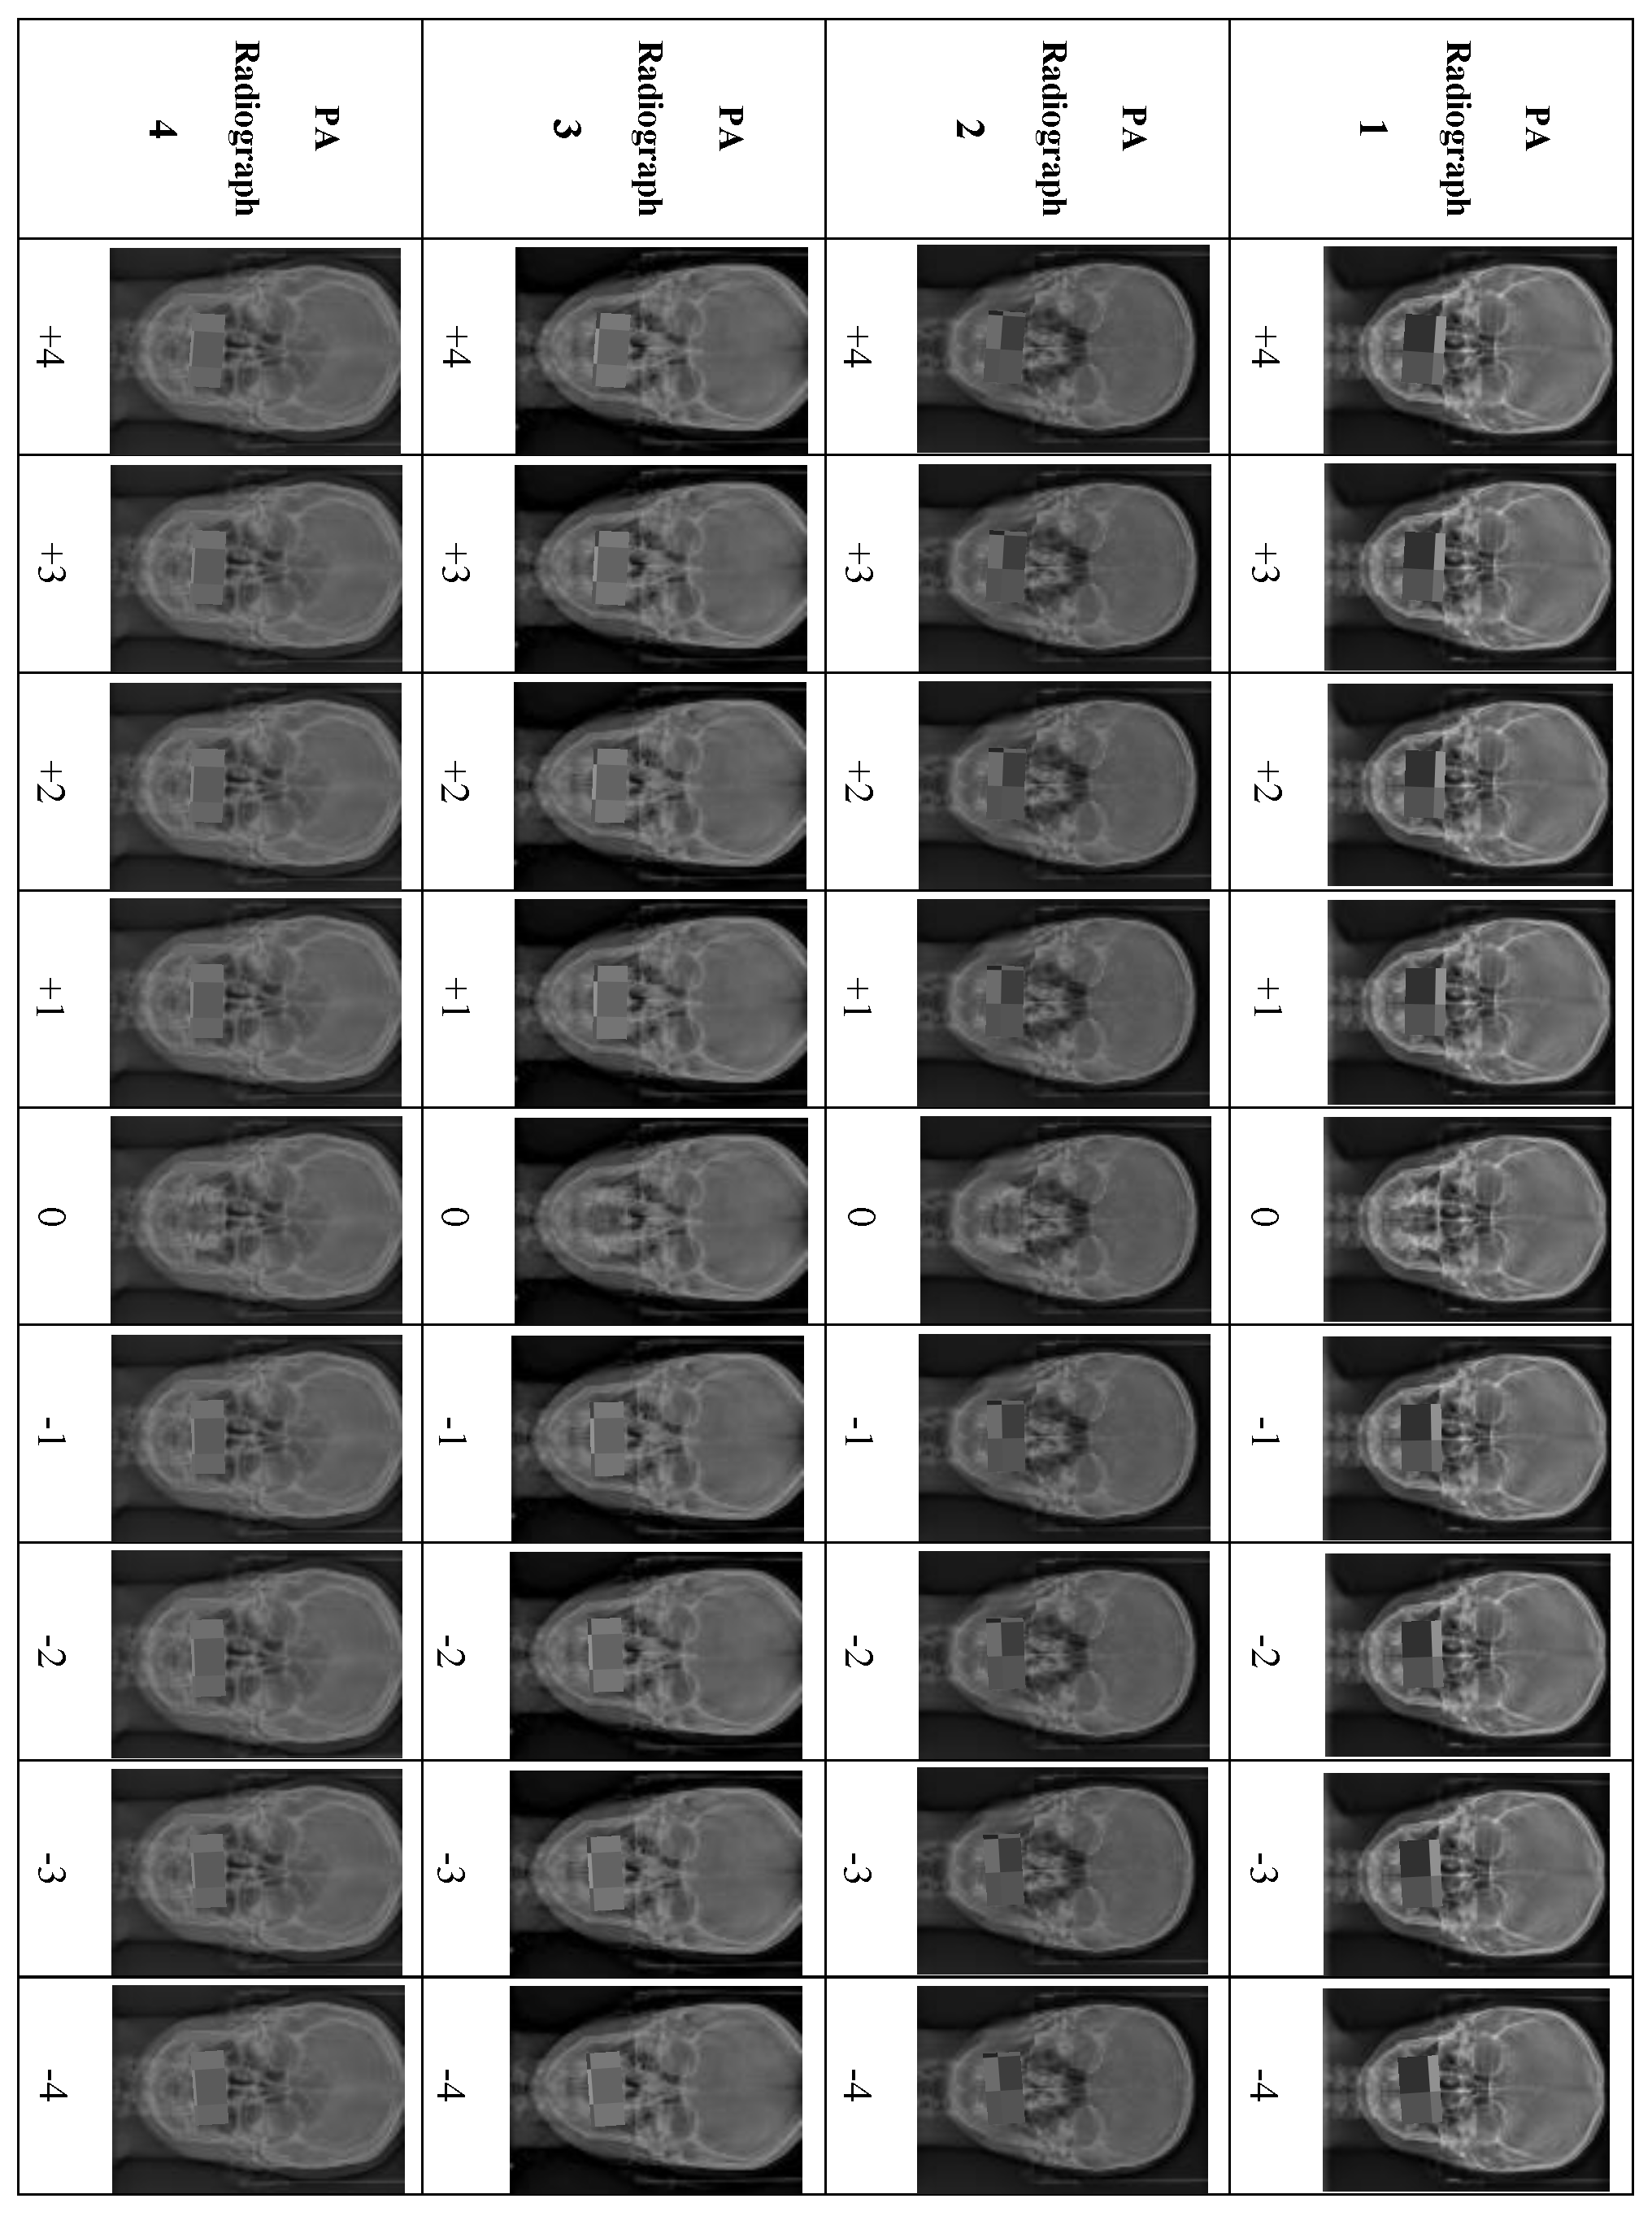

Eighteen PA cephalometric radiographs were excluded because they did not meet the inclusion criteria. Four PA cephalometric radiographs, representing two men and two women, were included in the study. Written informed consent was obtained from the four patients to use their PA radiographs with all the desired manipulations. For each PA radiograph, the upper and lower teeth in occlusion were cropped and manipulated to create different degrees of OC using Photoshop (Adobe Photoshop 9.0, San Jose, CA, USA). For accurate manipulation, the true horizontal line was used as a reference to rotate the OP in each PA image digitally. The OP in the original PA image was rotated in 1° increments from 1° to 4° in both directions. Accordingly, a set of nine manipulated PA images exhibiting various degrees of OCs based on the cut-off points of the newly developed OCI were prepared from each PA image. Each PA radiograph was manipulated to produce eight PA images representing Grades I to III of the OCI, with 1° representing Grade I, 2° and 3° representing Grade II, and 4° of OC representing Grade III (four right-sided and four left-sided), and the ninth manipulated PA image representing Grade 0 (0°). Thus, the four PA radiographs produced 36 manipulated PA images (Figure 1).

Figure 1.

Illustration of the manipulations of all the PA cephalometric radiographs, +1° to +5° (OC at the left side), and −1° to −5° (OC at the right side).